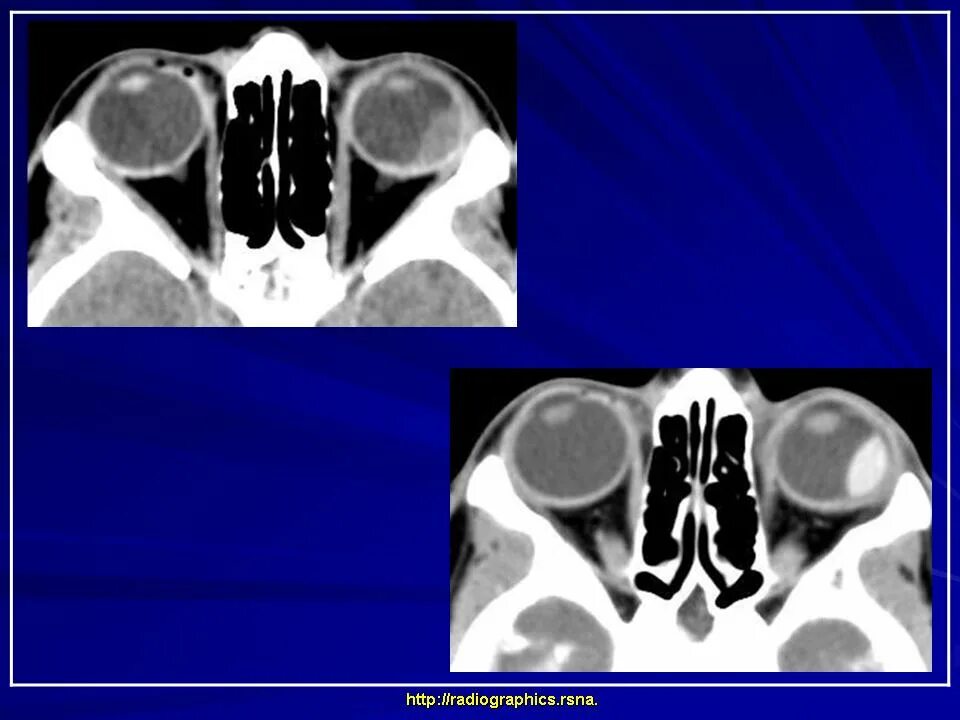

Данные кт